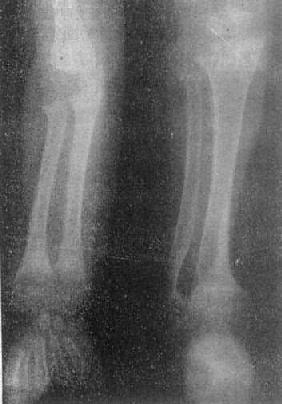

图2-1-8 前臂及小腿骨骨质软化—佝偻病骨质普遍密度减低,骨皮质薄,边缘不清,骨小梁

模糊,骨变弯、变形。干骺端宽大呈杯口状变形,骺与干骺干骺端距离增宽。骺边缘模糊。腕骨出现少

骨质软化的X线表现主要是由于骨内钙盐减少而引起的骨密度减低,以腰椎和骨盆为明显。与骨质疏松不同的是骨小梁和骨皮质边缘模糊,系因骨组织内含有大量未经钙化的骨样组织所致(图2-1-8)。由于骨质软化,承重骨骼常发生各种变形(图2-1-9)。此外,还可见假骨折线,表现为宽约1~2mm的光滑透明线,与骨皮质垂直,边缘稍致密,好发于耻骨支、肱骨、股骨上段和胫骨等。

佝偻病的一般X线表现是全身骨骼由于软骨基质钙化不足和骨样组织不能钙化,再加上原有的骨结构被吸收而发生普遍性骨质软化、密度减低,骨小梁稀少、粗糙,骨皮质变薄、分层等改变,骨结构由于骨组织内有大量无钙盐沉积的骨样组织的存在而显示模糊、毛糙。

具有典型X线表现的骨骼是在长骨干骺端,特别是在幼儿发育较快的尺桡骨远端、胫骨、肱骨上端、股骨下端和肋骨的前端等。较早的变化在骺板,由于软骨基质钙化不足,临时钙化带变得不规则、模糊、变薄,以至消失。干骺端中间带曲折变形而凹陷,明显者呈杯口状变形,其边缘因骨样组织不规则钙化而呈毛刷状致密影,干骺端宽大。骺出现延迟,密度低,边缘模糊,乃至不出现。骺与干骺端的距离由于骺板软骨增生、肥大、堆积、不骨化而增宽。干骺端边缘出现骨剌乃系骨皮质向干骺端方向延伸所致(图2-1-8)。肋骨前端由于软骨增生而膨大,形成串珠肋,X线表现肋骨前端呈宽的杯口状。由于骨质软化,承重的长骨常弯曲变形,在下肢发生膝内翻(O形腿)或膝外翻(X形腿)。少数例可发生青枝骨折或假性骨折。